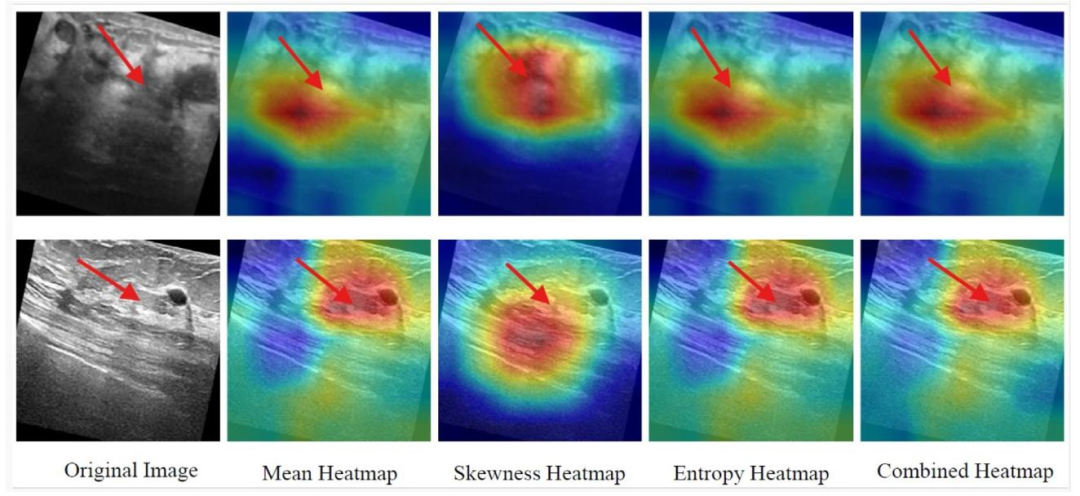

Fig. 5. SFMOV-based heatmap visualization showing a malignant ultrasound image detected as malignant (row 1) and a benign ultrasound image detection as benign (row 2).Red arrows represent the abrupt interface between healthy tissue and tumor.

图5. 基于SFMOV的热图可视化,展示了被检测为恶性的恶性超声图像(第1行)和被检测为良性的良性超声图像(第2行)。红色箭头表示健康组织与肿瘤之间的突变界面。